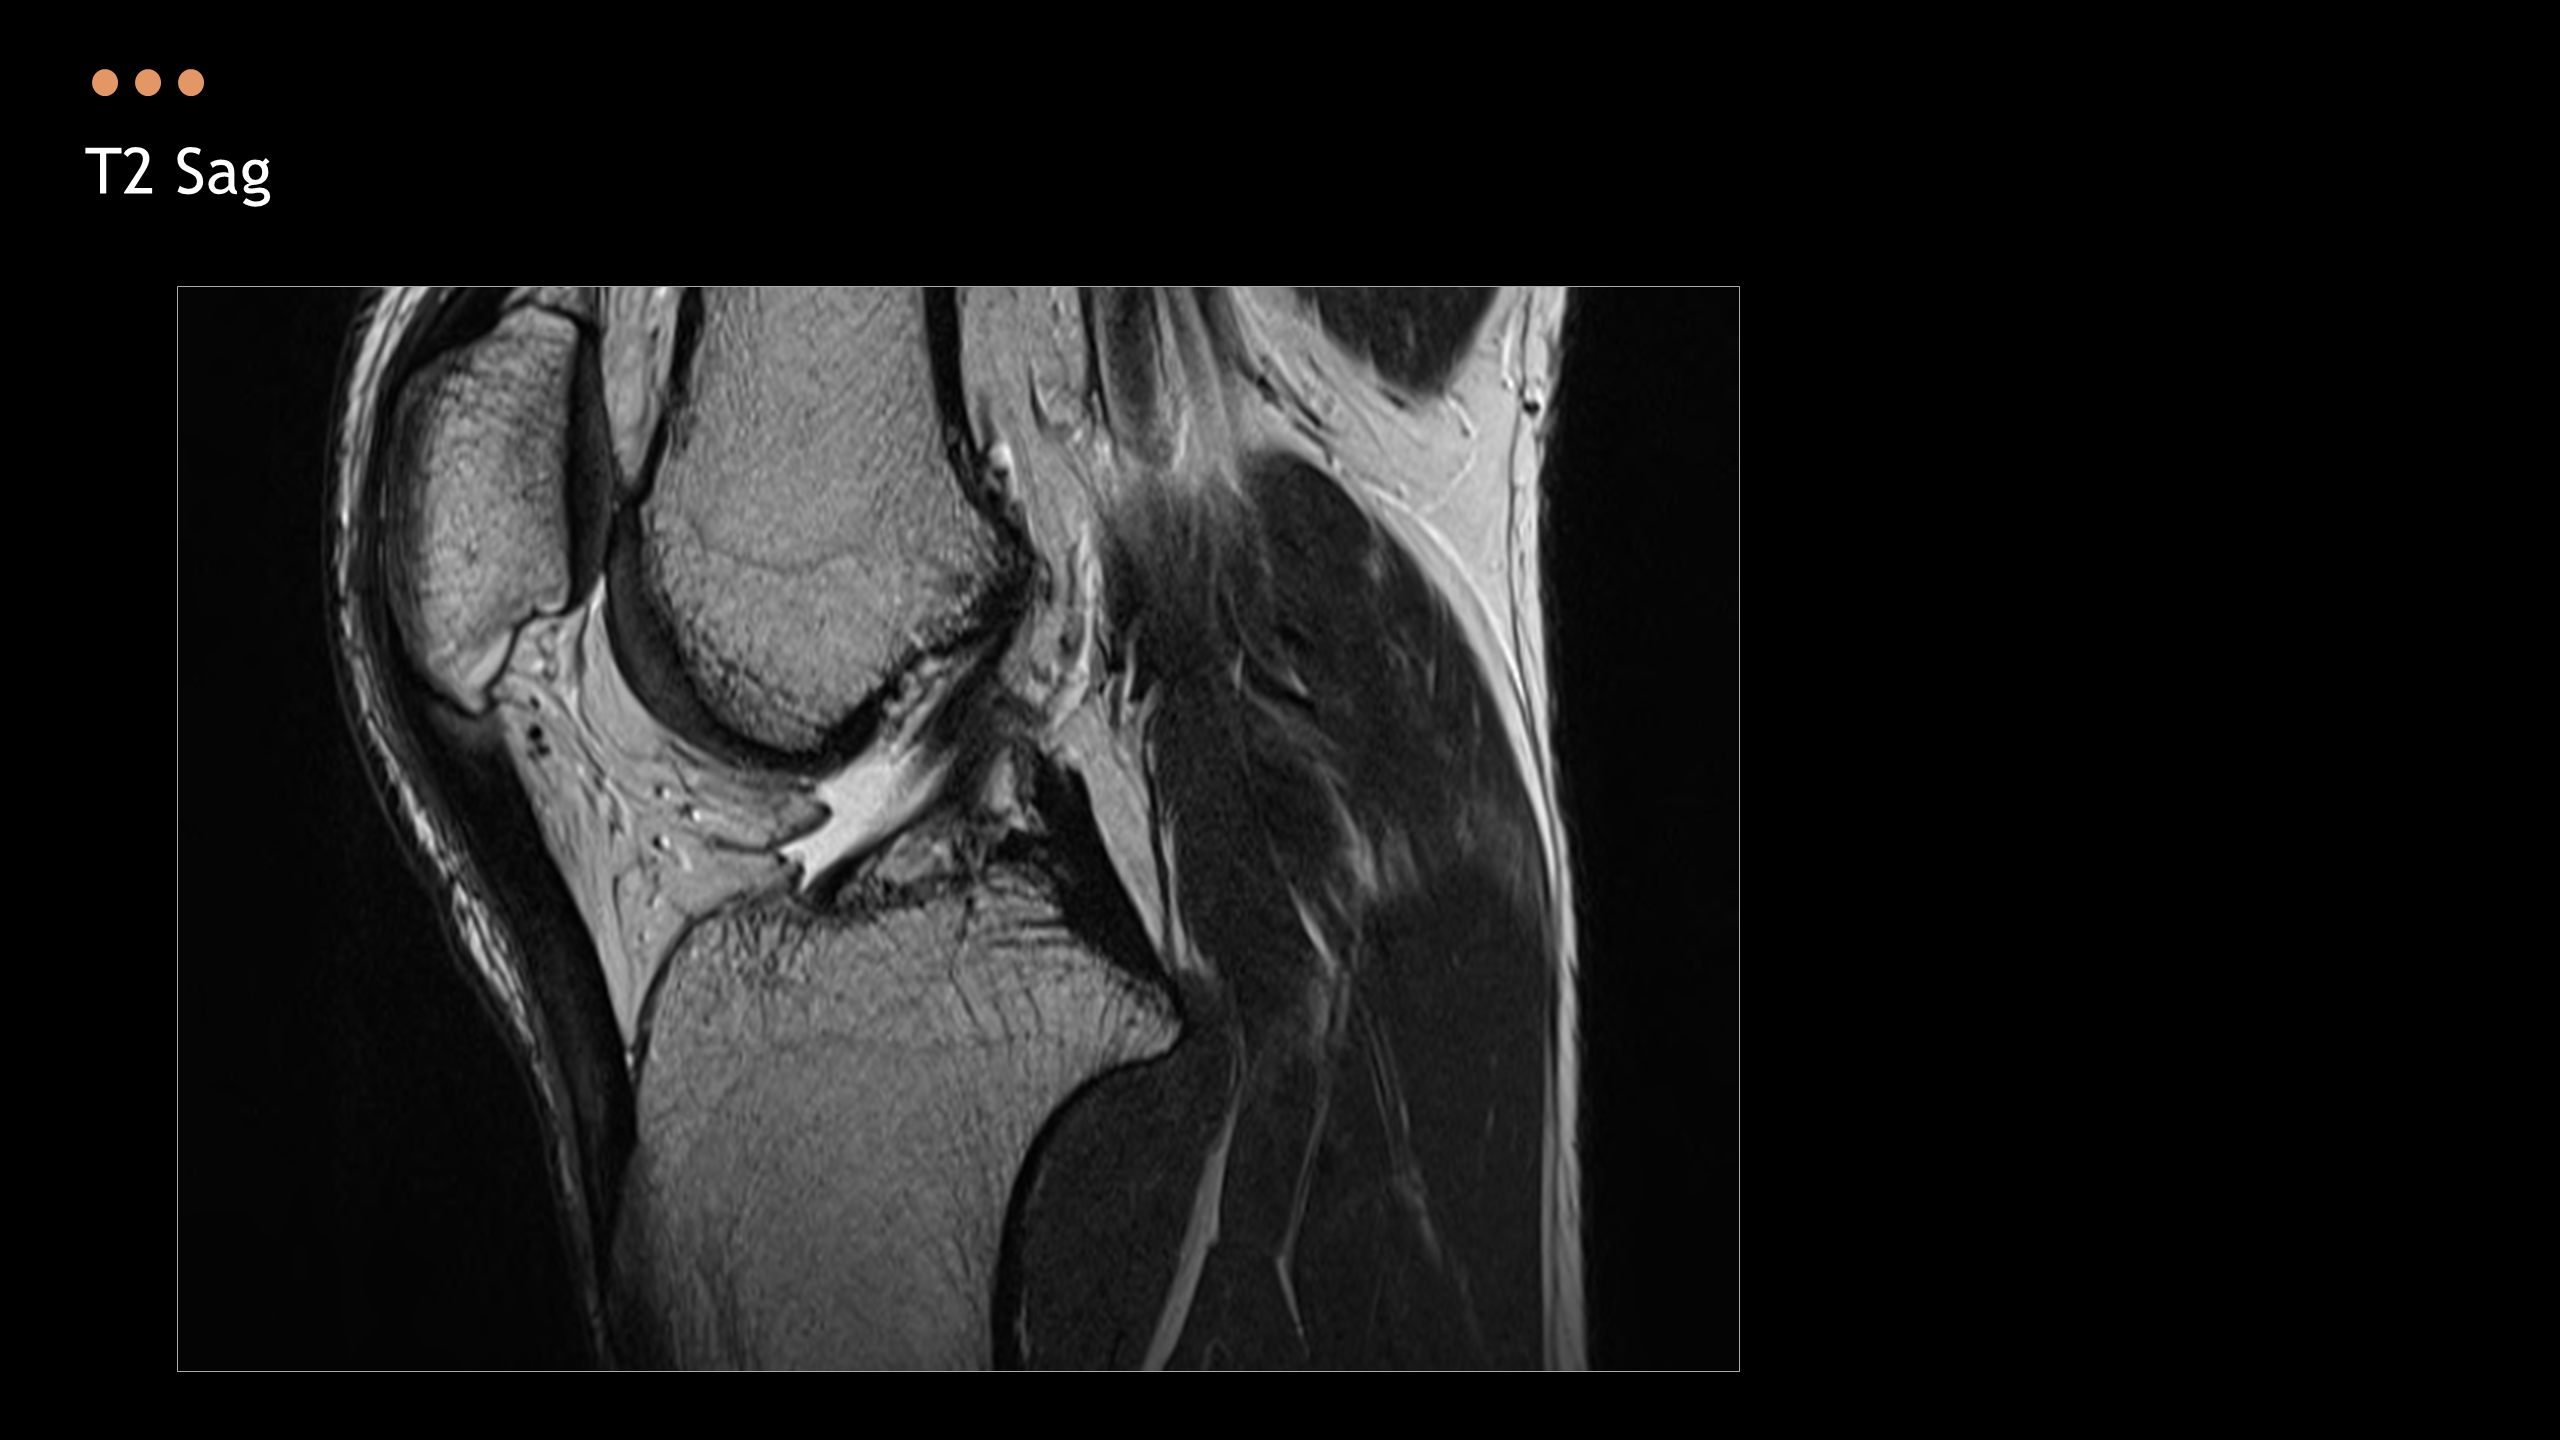

주제: The Knee MRI Approach

강사: 신민섭

아래의 Normal Knee MR Anatomy를 숙지하고 오셔야, 강의에 어려움이 없습니다.